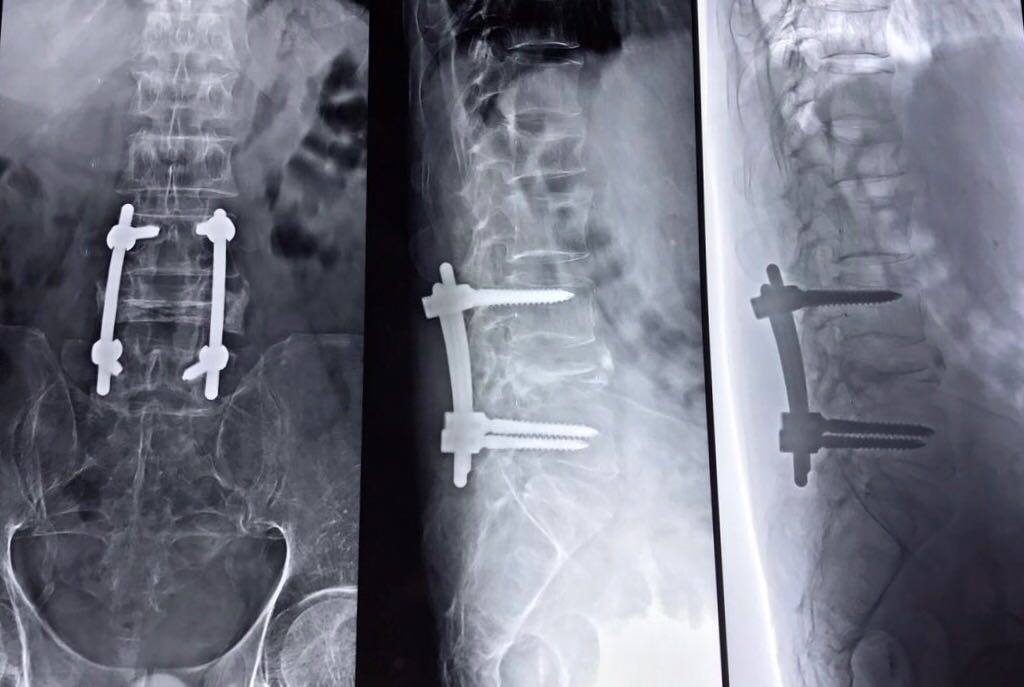

• Surgical hardware is applied to the spine to help enhance the fusion rate. Pedicle screws and rods are attached to the back of the vertebra and an interbody fusion spacer is inserted into the disc space from one side of the spine.

Using the minimally invasive procedure involves a small incision in the back. Using a portable X-ray machine, the surgeon locates the diseased vertebral levels. Making the smallest incision possible, the surgeon uses a combination of dilators and tubular retractors to access the vertebra and remove the degenerative disc. An implant with bone graft is placed in the empty space, this realigns the vertebral bones and relieves pressure on the nerve roots.